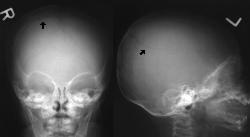

Skull

2 views RM60

X-ray of a year old boy showing skull

fracture